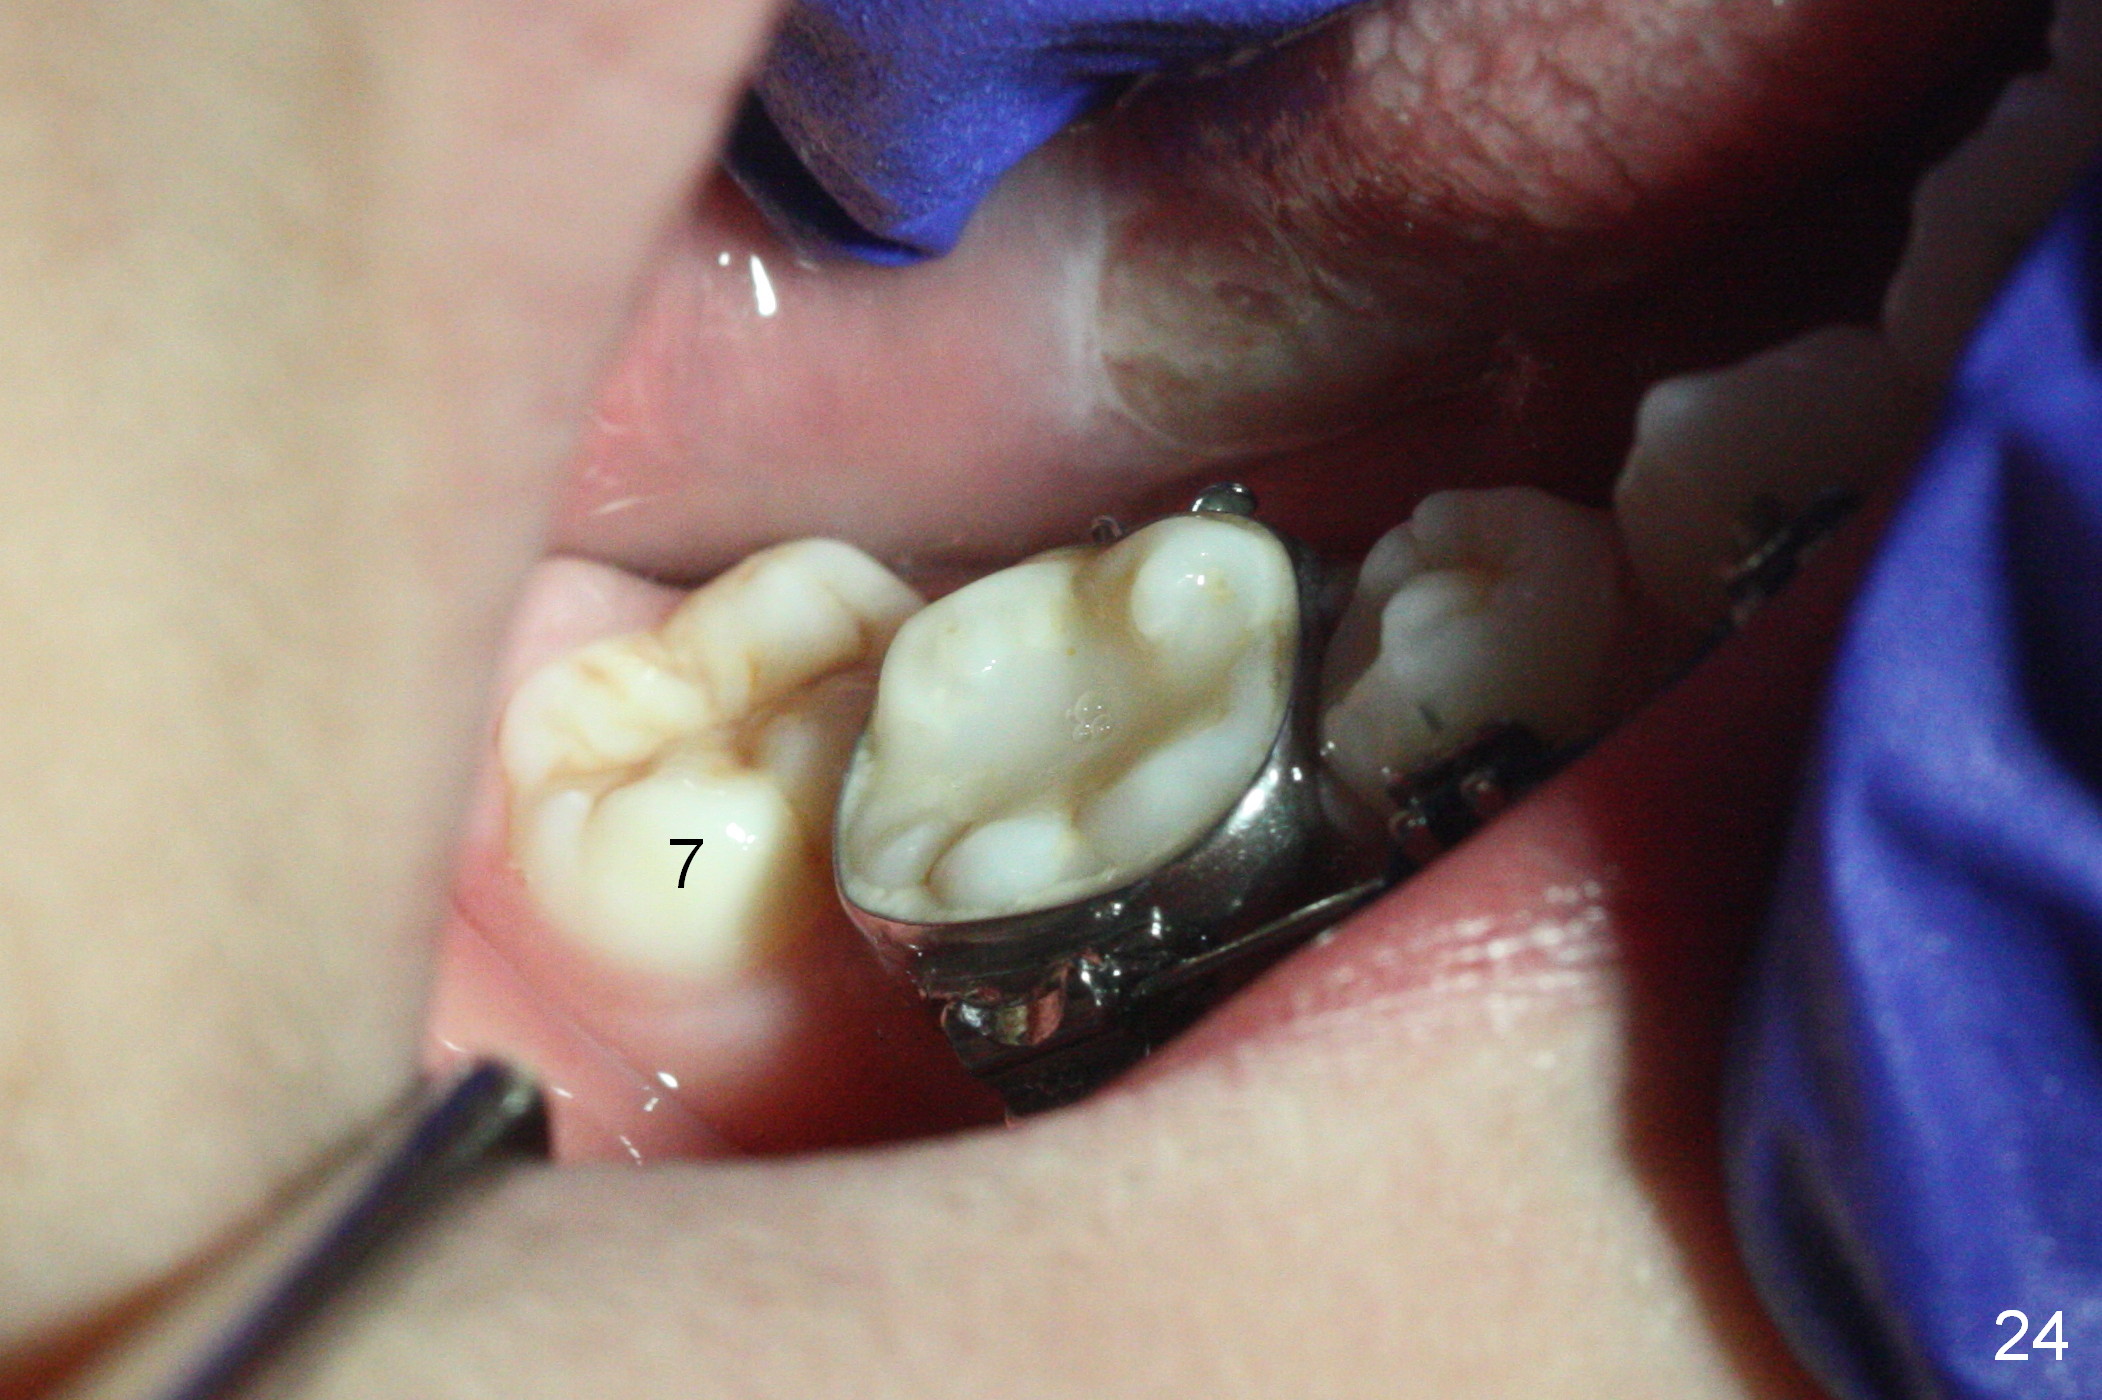

One month of open coil spring between UR1 and 3 (18 ss), power chain is placed with 3 loops between UR2 and 3 and 5 loops between UR 1 and 2 (Fig.21, sling shot). One month later, bracket is placed at UR2 (upside down) and 16 niti wire is engaged (Fig.22). While L3-3 is laced, power chain is placed between LR 3 and 5 with intention to mesialize the latter (Fig.23 arrow) so that there will be enough space to de-rotate LR7 (Fig.24). Can we at the same time place a separator between LR 6 and 7 to mesialize LR6 and distalize LR7?